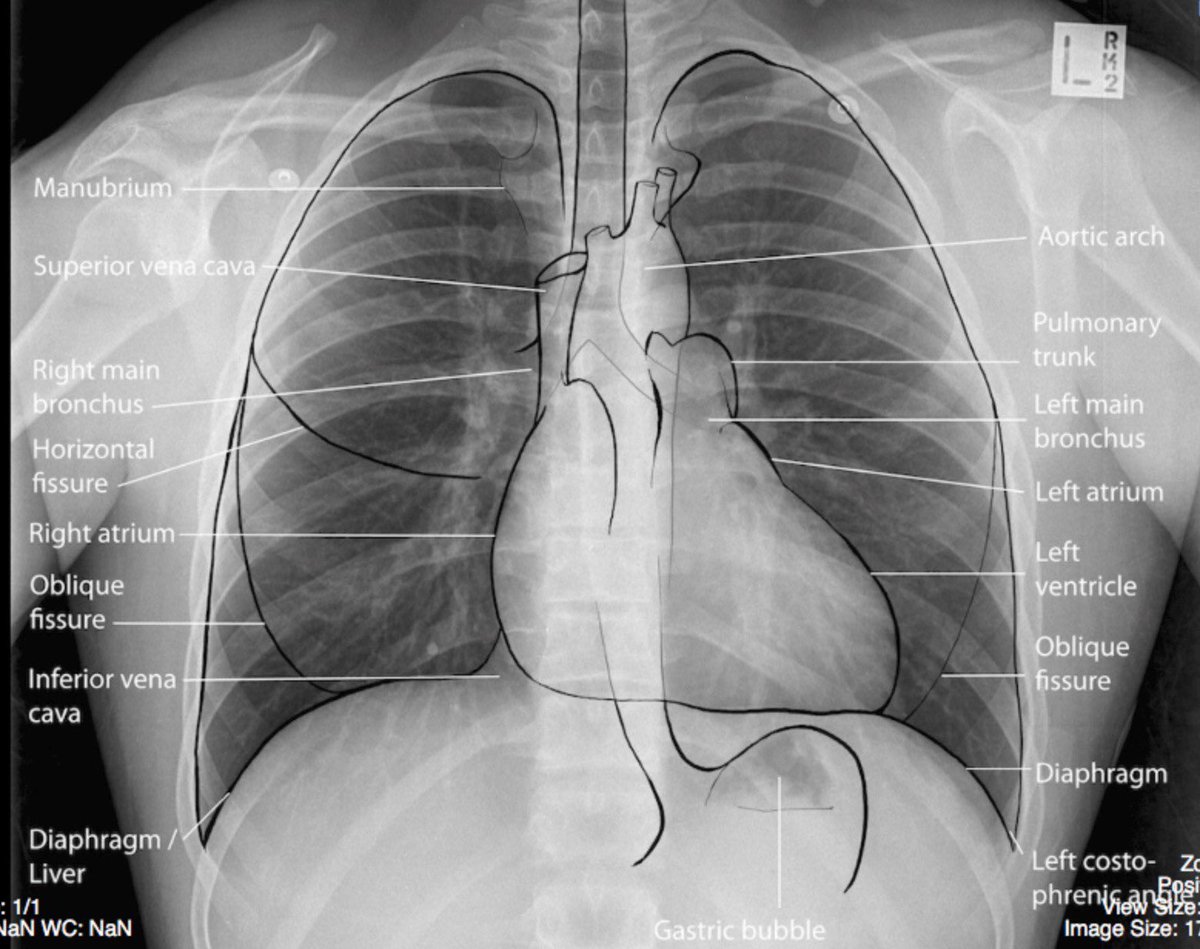

هذا شرح بسيط سويته لكيفية قرأة صور الـchest x-ray .. الله يكتب فيه النفع والفائده للجميع!

طبعاً. الصوره الي شرحت عليها صورة رئة مريض .. فممكن التحديد ما كان واضح للبعض ! هذه صورة من قوقل مشروح على صوره رئة طبيعيه كل التحديدات المهمه